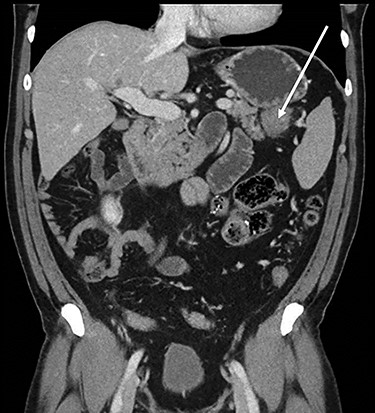

Abdominopelvic CT scan disclosed a 3.7-cm mass, between the tail of the pancreas and the splenic hilum, causing a narrowing of the splenic vein and splenomegaly (Figs 1–3).

Coronal CT scan of abdomen, selected image from a pancreatic protocol, portal venous phase. A 3.7-cm mass, between the tail of the pancreas and the splenic hilum, corresponding to a peritoneal implant (arrow).